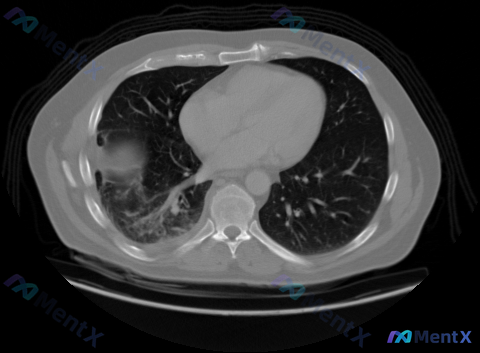

看到一个胸部CT肺窗的病例资料,整理了一下分析思路: 首先看影像表现:右肺上叶有明显的局限性慢性纤维增殖性病变,形态不规则,边界毛糙,有纤维条索影、胸膜牵拉凹陷,还有牵拉性支气管扩张,局部肺容积缩小(叶间裂向内移)。左肺实质和气道看起来都正常。 初步判断,这个病灶的慢性纤维增殖特征很突出,首先想到的...

看到一个胸部CT肺窗病例,整理了一下分析思路,大家一起讨论。 主诉与现病史:无直接提供,但从影像来看有局灶性病变。 检查/检验:本次提供的是胸部CT肺窗横断面图像,清晰度良好,无明显伪影。 影像信息:层面约在主动脉弓水平,气管居中,双肺透亮度大致对称。右肺(图像左侧)上叶可见多发性囊泡状、网格状透亮...

看到这张胸部CT肺窗的影像资料,整理出来给大家分享,顺便梳理一下我的分析思路。 一、病例影像基本信息 这是胸廓上部层面的胸部CT肺窗影像,可见双侧肺尖及上肺野,异常表现总结如下: 1. 核心异常:右肺上叶尖后段(靠近纵隔胸膜下)可见大范围不规则实变,伴纤维增殖改变,局部肺透亮度明显降低,肺纹理结构紊...